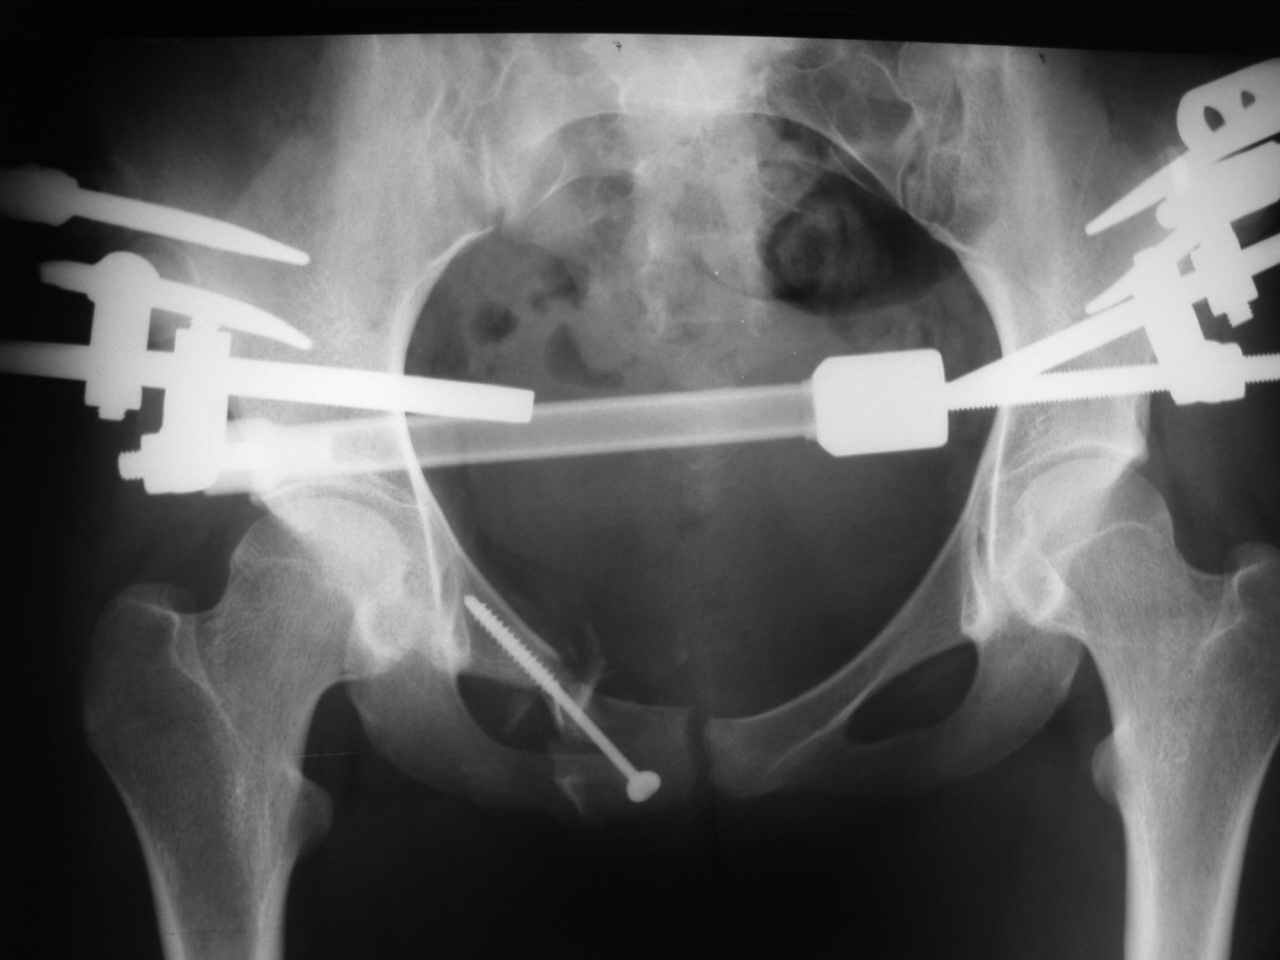

Уважаемые коллеги! К нам поступила молодая девушка 18 лет с оскольчатым переломом лонной и седалищной кости справа, после травмы прошел 1 месяц. Нужно ли вообще оперировать, стоит ли гнаться за анатомией? Или сделать комбинированный остеосинтез?

ЕЧ -Прямая проекция только не дает полной информации о характере повреждений заднего отдела. Судя по механизму травмы, задняя крестцово-подвздошная связка должна пострадать помимо видимого на Рг грамме трансфораминального перелома справа. КТ и инлет проекция были бы полезны.

В принцине анатомия - функционально обоснованное пространственное расположение образований, составляющих тазовое кольцо. Если внимательно присмотреться даже к этому снимку - можно выявить грубую деформацию, сравнимую со смещением по длине, ширине и под углом диафиза длинной трубчатой кости. Кроме того имеет место импрессионный перелом боковых масс крестца, ротационное смещение правой половины таза, грубое нарушение непрерывности костного остова по лобковой дуге с линейным и ротационным

смещением справа, некорректная установка головки правого бедра с вытекающими последствиями. Так что уж и не знаю надо ли гнаться за анатомией или физиологией или биомеханикой. При переломах бедра и голени этих вопрсов уже не возникает.

Проблема этой девушки не спереди а сзади в поврежденном крестцово-подвздошном сочленении с той же стороны. Судя по снимку есть смещение. Нужно сделать снимки на вход и выход таза (outlet, inlet) и стоит добавить КТ и тогда решить об операции. Судя по снимку девушка нуждается в вправлении и фиксации или артродезе крест-подвзд.